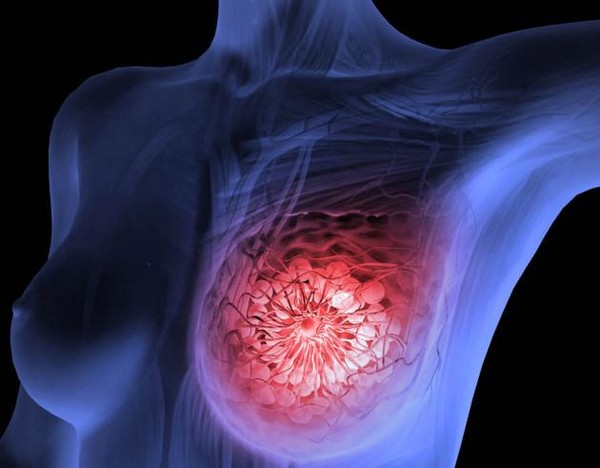

유방암은 여성에게 가장 흔한 암 중 하나로, 조기 발견과 치료가 생존율에 큰 영향을 미칩니다. 이번 포스팅에서는 유방암 초기증상, 2기 생존율, 수술 후 회복기간에 대해 자세히 알아보겠습니다.

1. 유방암 초기증상

유방암 초기에는 증상이 명확하지 않을 수 있지만, 아래와 같은 변화를 주의 깊게 살펴보는 것이 중요합니다.

주요 초기증상

- 유방에 덩어리(종괴) 발생

유방이나 겨드랑이 부근에서 통증이 없는 단단한 혹이 만져질 수 있습니다. - 유방 모양 변화

한쪽 유방이 비대칭적으로 변하거나 크기와 모양이 변합니다. - 피부 변화

유방 피부가 오렌지 껍질처럼 두꺼워지거나 함몰됩니다. - 유두 이상

유두에서 분비물이 나오거나, 유두가 함몰되는 증상이 나타날 수 있습니다. - 통증

초기에는 드물지만, 유방이나 겨드랑이에 지속적인 통증이 동반될 수 있습니다.